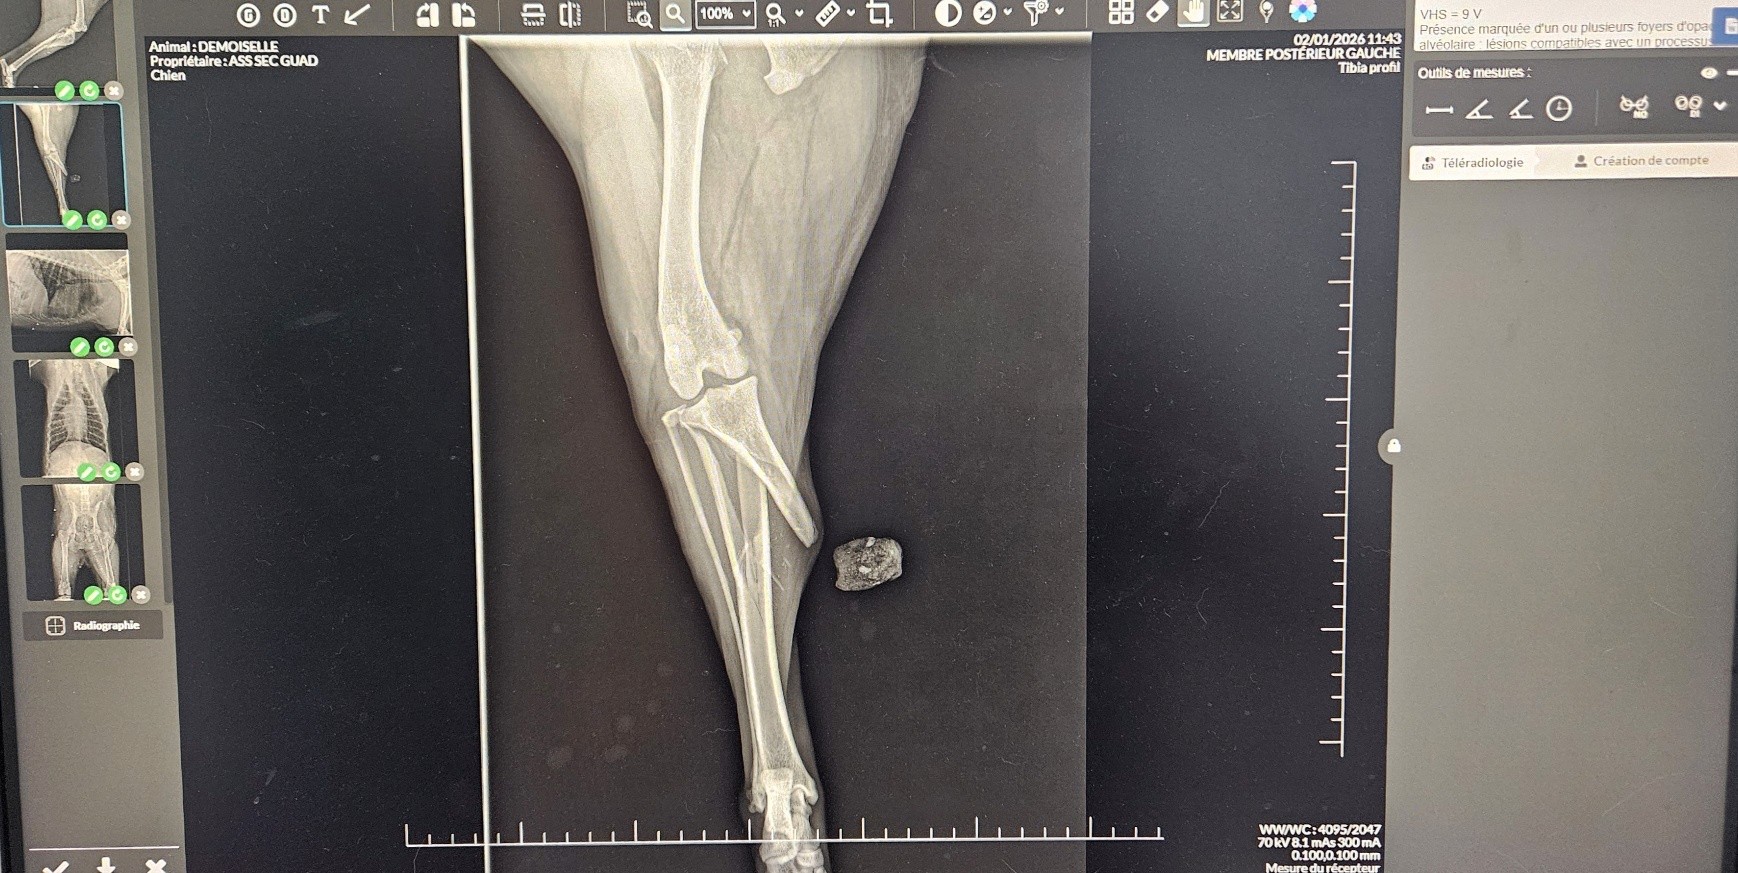

Radiographie Numérique

Une radiographie numérique de dernière génération et un capteur plan avec résolution pixel performante permettent de réaliser des clichés de grande qualité.

Leur interprétation est aidée par un logiciel d'intelligence artificielle.

C'est un outil diagnostique indispensable dans la recherche de multiples pathologies.